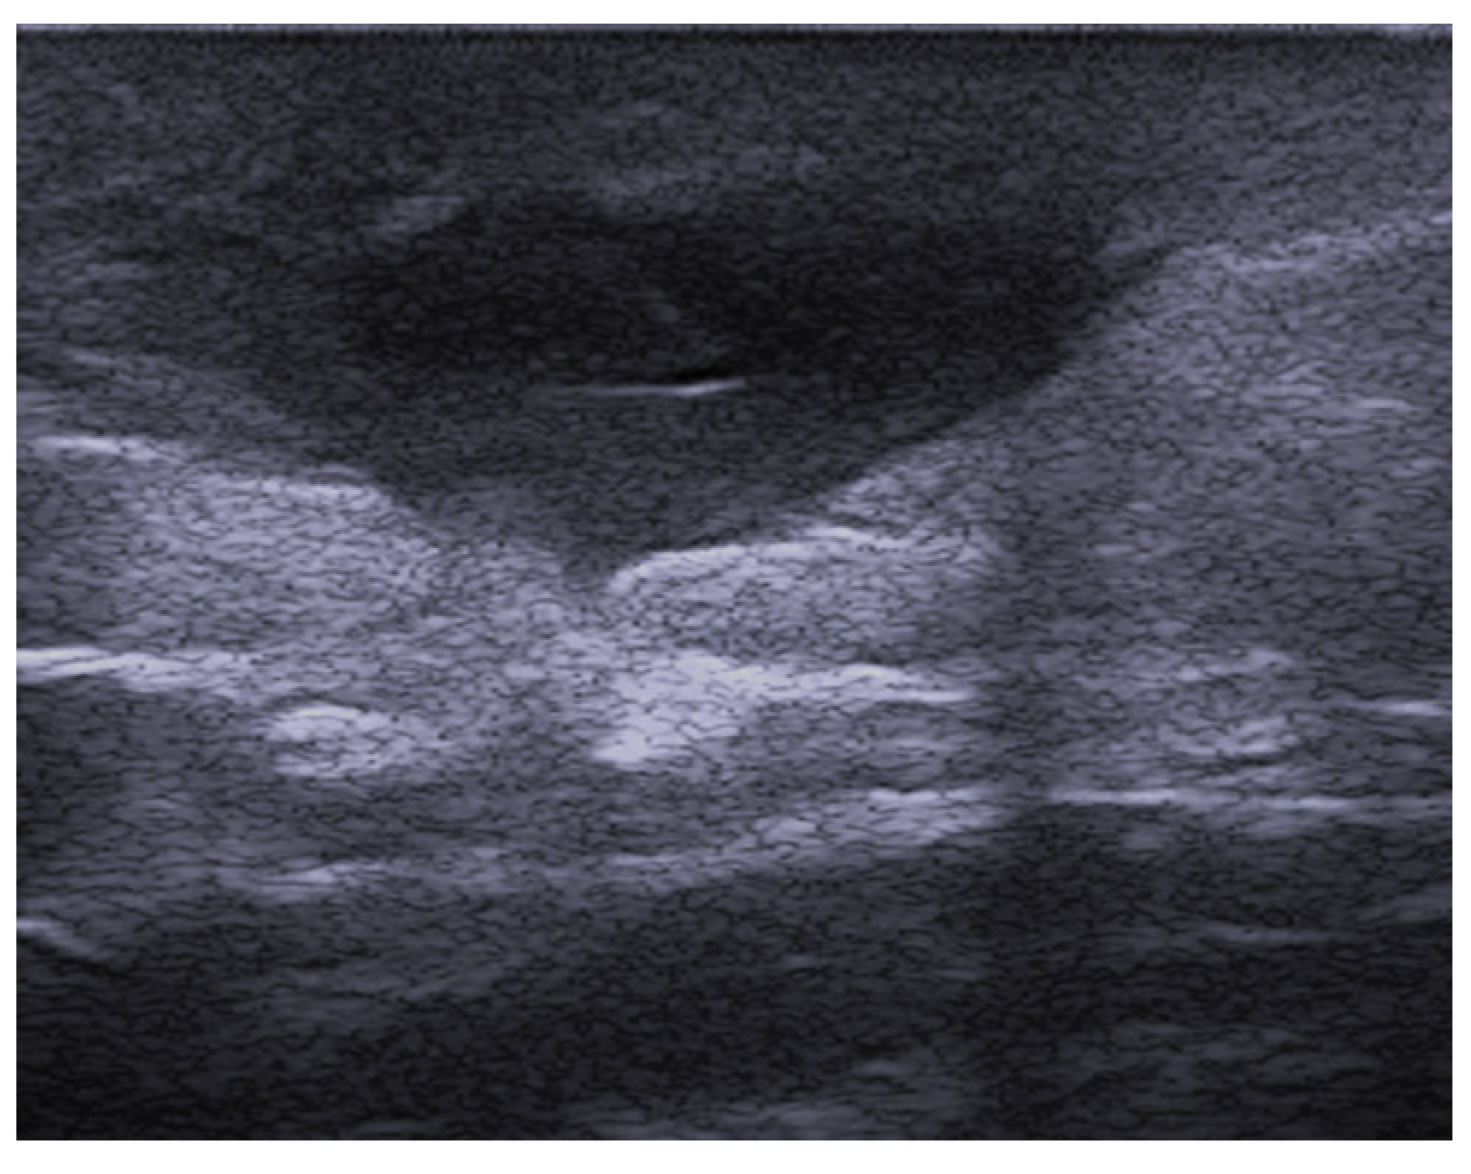

- Dini, V.; Michelucci, A.; Granieri, G.; Zerbinati, N.; Margiotta, F.M.; Romanelli, M. Evaluation of post-surgical complications of hidradenitis suppurativa lesions explored with presurgical ultra-high frequency ultrasound mapping. J. Wound Care 2024, 33, S10–S16. [Google Scholar] [CrossRef]

- Michelucci, A.; Fidanzi, C.; Manzo Margiotta, F.; Granieri, G.; Salvia, G.; Janowska, A.; Romanelli, M.; Dini, V. Presurgical Mapping with Ultra-high Frequency Ultrasound of Hidradenitis Suppurativa Lesions Treated with Wide Local Excision and Secondary Intention Healing. Dermatol. Surg. 2025, 51, 36–39. [Google Scholar] [CrossRef]